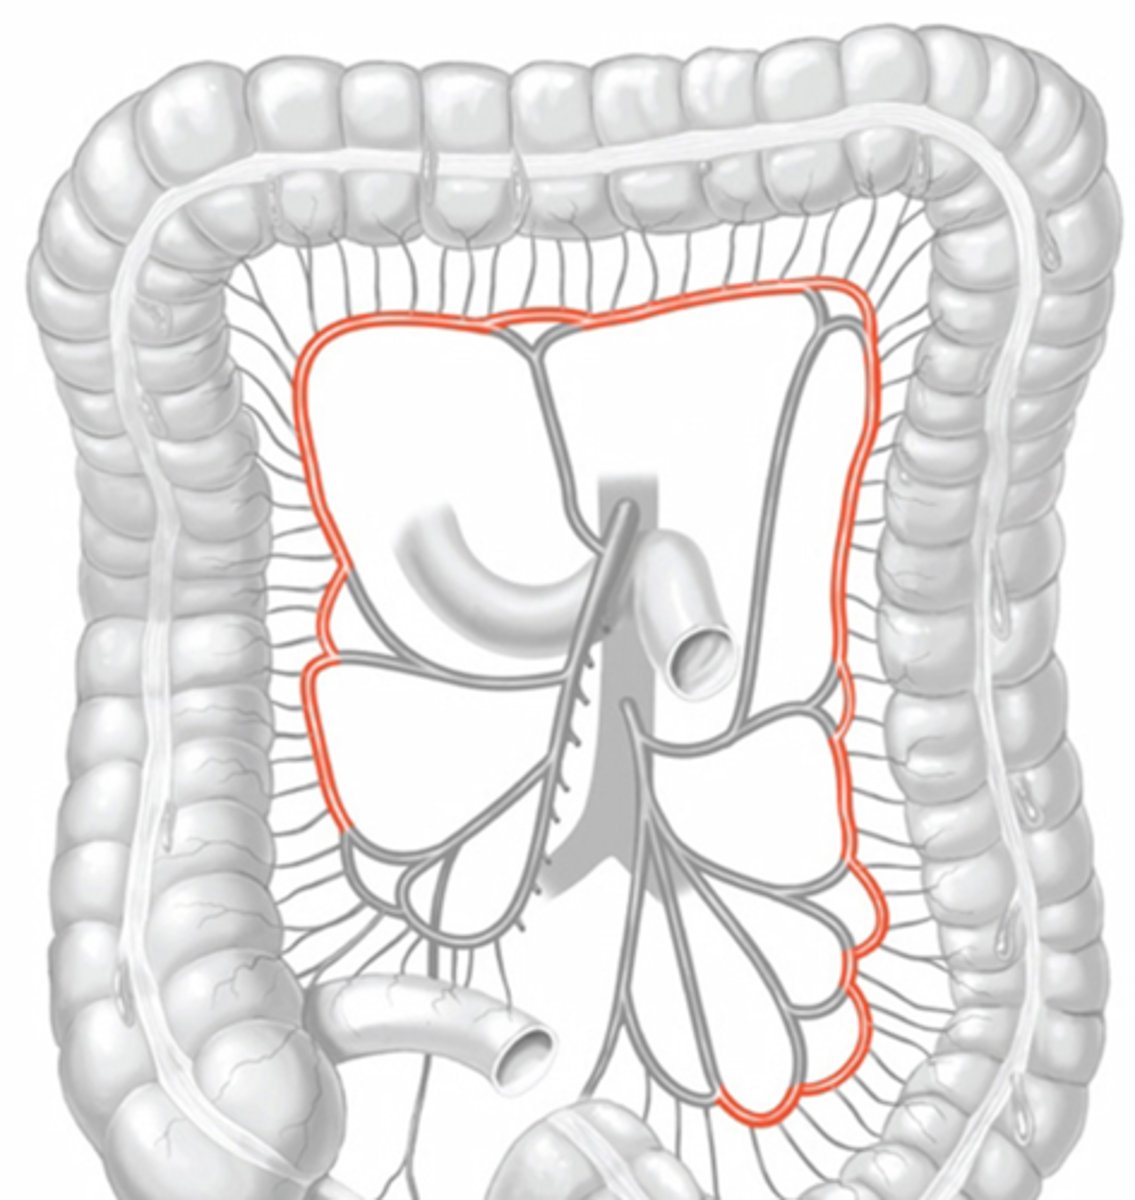

jejunum

ileum

ascending colon

transverse colon

descending colon

sigmoid colon

superior mesenteric artery

jejunal and ileal arteries

ileocolic artery

right colic artery

middle colic artery

inferior mesenteric artery

left colic artery

sigmoidal arteries

marginal artery